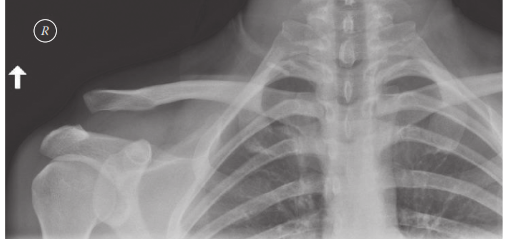

This is a radiograph of a patient brought to the emergency department after being knocked off his bicycle in …

A 32-year-old woman is admitted after a fall from her bicycle. She has an isolated injury to her left upper l…